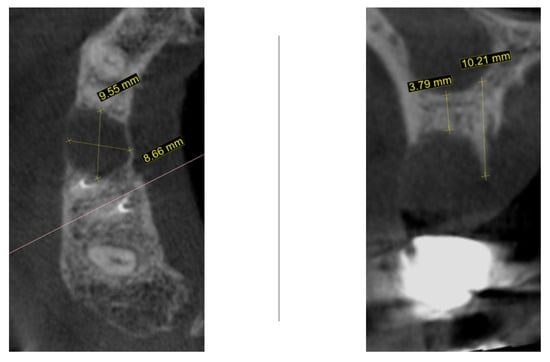

One month later, cone-beam computed tomography (CBCT) was performed to assess the morphology of the post-extraction site (Figure 2). For the region of interest (second right maxillary premolar), digital impressions were obtained using iTero Element Flex (Align Technology, Inc., Tempe, AZ, USA) and processed with Exoplan software, version 3.1 Rijeka (Exocad GmbH, Darmstadt, Germany). The iTero scanner applies a primarily surface-based registration complemented by anatomical landmarks, ensuring accurate fit and alignment. Using confocal imaging, it acquires detailed surface topography through point-and-stitch reconstruction, producing high-precision 3D models of teeth and soft tissues without the need for powder. Digital scans obtained during planning and at 3, 4, and 8 months post-surgery were superimposed using Exoplan (Exocad GmbH) software. Two-dimensional changes were assessed: (1) horizontal dimension—from the platform of the planned implant position to the corresponding buccal mucosal point, and (2) vertical dimension—from the implant platform to the buccal mucosal margin of the planned or placed restoration. The cross-sectional view demonstrated a large radiolucent zone with width of 9.5 mm and bucco-lingual dimension of 8.6 mm. In the sagittal plane, the residual vertical bone height measured 3.7 mm with a preserved palatal bony wall (10.2 mm). Although the assessment of these CBCT findings usually necessitates a bone augmentation procedure before implant placement, an alternative decision was taken to wait until the natural healing process is complete.

Figure 2.

CBCT one month following atraumatic extraction.